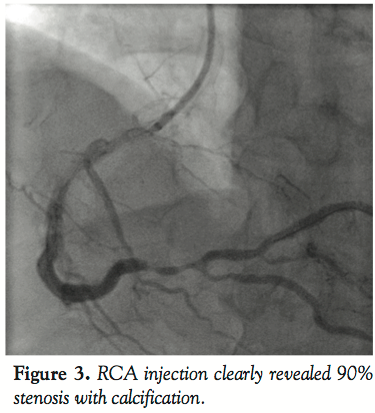

The post-procedural recovery of the patient was uneventful and thus he was discharged from the hospital with double anti-platelet therapy (100 mg of aspirin and 75 mg of clopidogrel sulfate) on the following day. One month later, the patient was re-admitted for PCI because of persistent chest pain on effort despite medical treatment. He was diagnosed 90% stenosis with severe calcification at the distal portion of the RCA by computed tomography. On the other hand, there was no stent thrombosis at the implanted stent lesion of LAD. We performed PCI of the RCA under local anesthesia and a 6 Fr sheath introducer was inserted into the right brachial artery. We inserted a 4 Fr multipurpose angiographic catheter into a DIO thrombus aspiration catheter to deliver it to the ascending aorta. The DIO was functionally stabilized to find the RCA ostium by manipulating the angiographic catheter. When the angiographic catheter successfully engaged the RCA ostium, we glided the DIO catheter forward and pulled out the angiographic catheter to perform angiography. RCA injection clearly revealed 90% stenosis with calcification. The lesion was crossed with a Neo’s Fielder guidewire (Asahi Intech Corporation), and pre-dilated with a 2.0 mm × 15 mm Lacrosse balloon catheter (Goodman Co. Ltd., Aichi) at 10 atm. We tried to deliver an Eagle eye IVUS catheter (Volcano Corporation), but it did not cross the lesion because of insufficient back-up force.